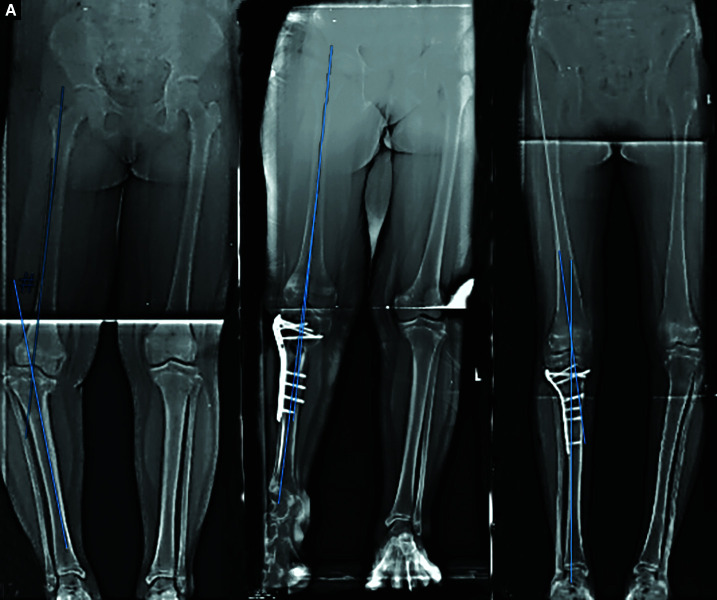

Background: Tibia vara is a three-dimensional deformity of the proximal tibia, varus, internal tibial torsion and procurvatum. It is an uncommon deformity with the surgical management varied. This study describes the outcomes of tibia vara management using a corrective transverse osteotomy in one centre.

Materials and methods: A retrospective cohort study was conducted involving eight patients with tibia vara (ten tibias). Consent was obtained for treatment using an acute corrective osteotomy. Measurements of Drennan's angle, the tibiofemoral angle (TFA) and the procurvatum angle were measured preoperatively and postoperatively both just after surgery and at 1 year. A validated questionnaire-the Knee Outcome Survey of Activity Daily Living (KOS-ADL)-was utilised to assess clinical function and outcome. Also recorded were the intraoperative and postoperative complications, the radiological lower limb alignments, the union rate and the recurrence of deformity.

Results: There were eight patients involved in this study with a total of ten tibias (six with unilateral tibias and two with bilateral tibias). The mean age of the patients was 11.3 years old (ranging from 8 to 15 years old) with most males (five males and three females). The affected tibias were 6 right sided and 4 left sided. Measurements of Drennan's angle, the TFA and the procurvatum angle were used to determine lower limb alignment preoperatively, postoperatively (immediate post-surgery) and at 1-year follow-up. Functional parameters were measured using the KOS-ADL. A descriptive analysis between the preoperative and postoperative variables was done. The mean for Drennan's angle was 21.6 (±5.2) preoperatively, 3.6 (± 2.3) postoperatively and 4.9 (±2.8) at 1-year follow-up. The TFA was improved from 22.6 (±6.1) preoperatively to 3.5 (±2.8) postoperatively and 4.4 (±2.0) at 1-year follow-up. The procurvatum angle was improved preoperatively from 8.20 (±7.5) to 2.40 (±2.5) postoperatively and 2.20 (±2.5) at 1-year follow-up. At the latest follow-up, the ADLS mean score was 98.5 (±2.6) while the SAS mean score was 97.5 (±3.3). The mean length follow-up period was 2 years (ranging from 1 year to 3 years). None of the patients developed postoperative complications with all achieving union without deformity recurrence in the period of observation.

Conclusion: This study revealed that acute correction via a corrective transverse osteotomy of the tibia is a safe and effective method in treating tibia vara.